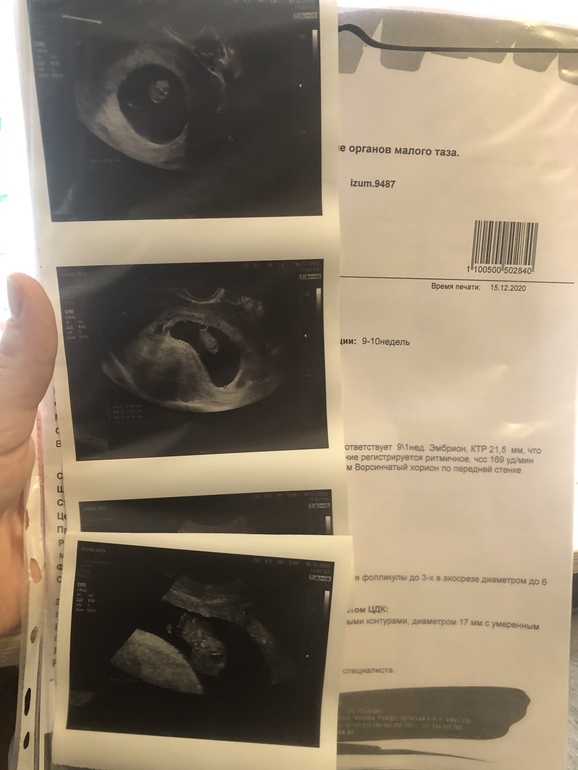

Узи 10 неделек

Метод Рамзи учитывает трансвагинальное узи до 8 недели По первому узи хорион вроде слева, это на мальчика)

15.12.2020